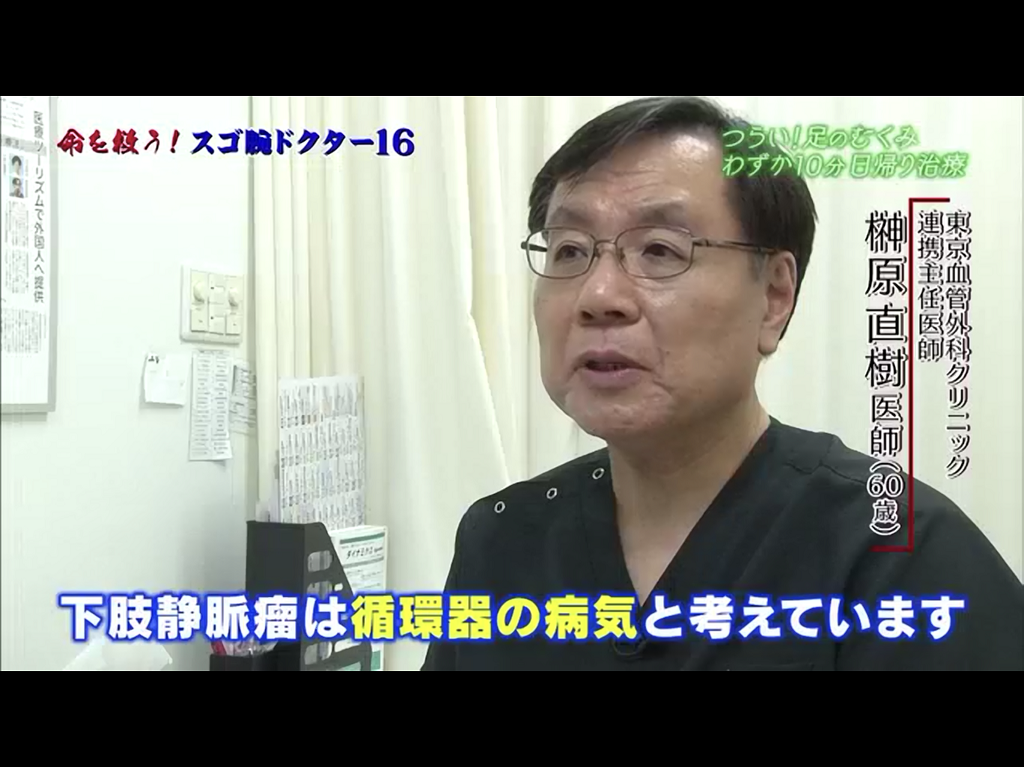

心臓血管外科医 榊原直樹 東京血管外科クリニック

下肢静脈瘤 治療法の変遷と進化 インタビュー ラジオ編 榊原医師 Youtube